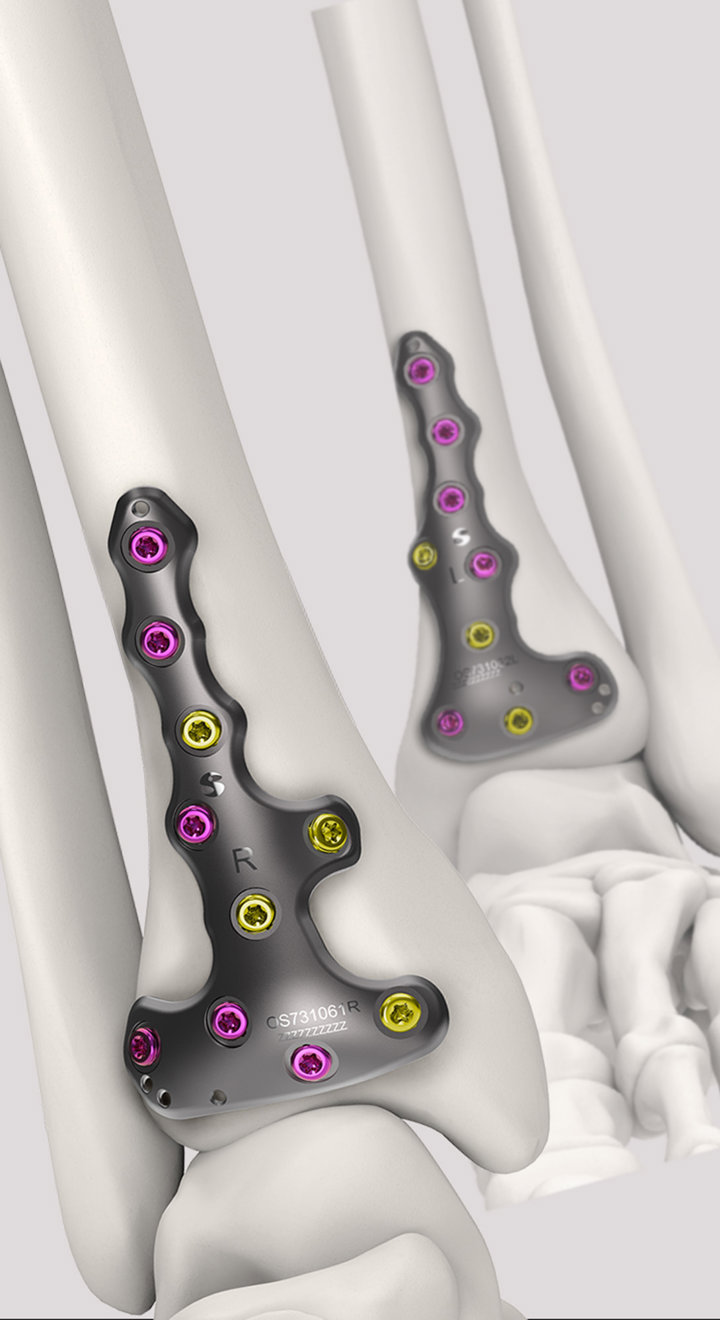

Volition® Ankle Fracture Plating

Evidence based ankle fracture plating solution. Anatomically designed to optimize the treatment of all types of ankle fractures.